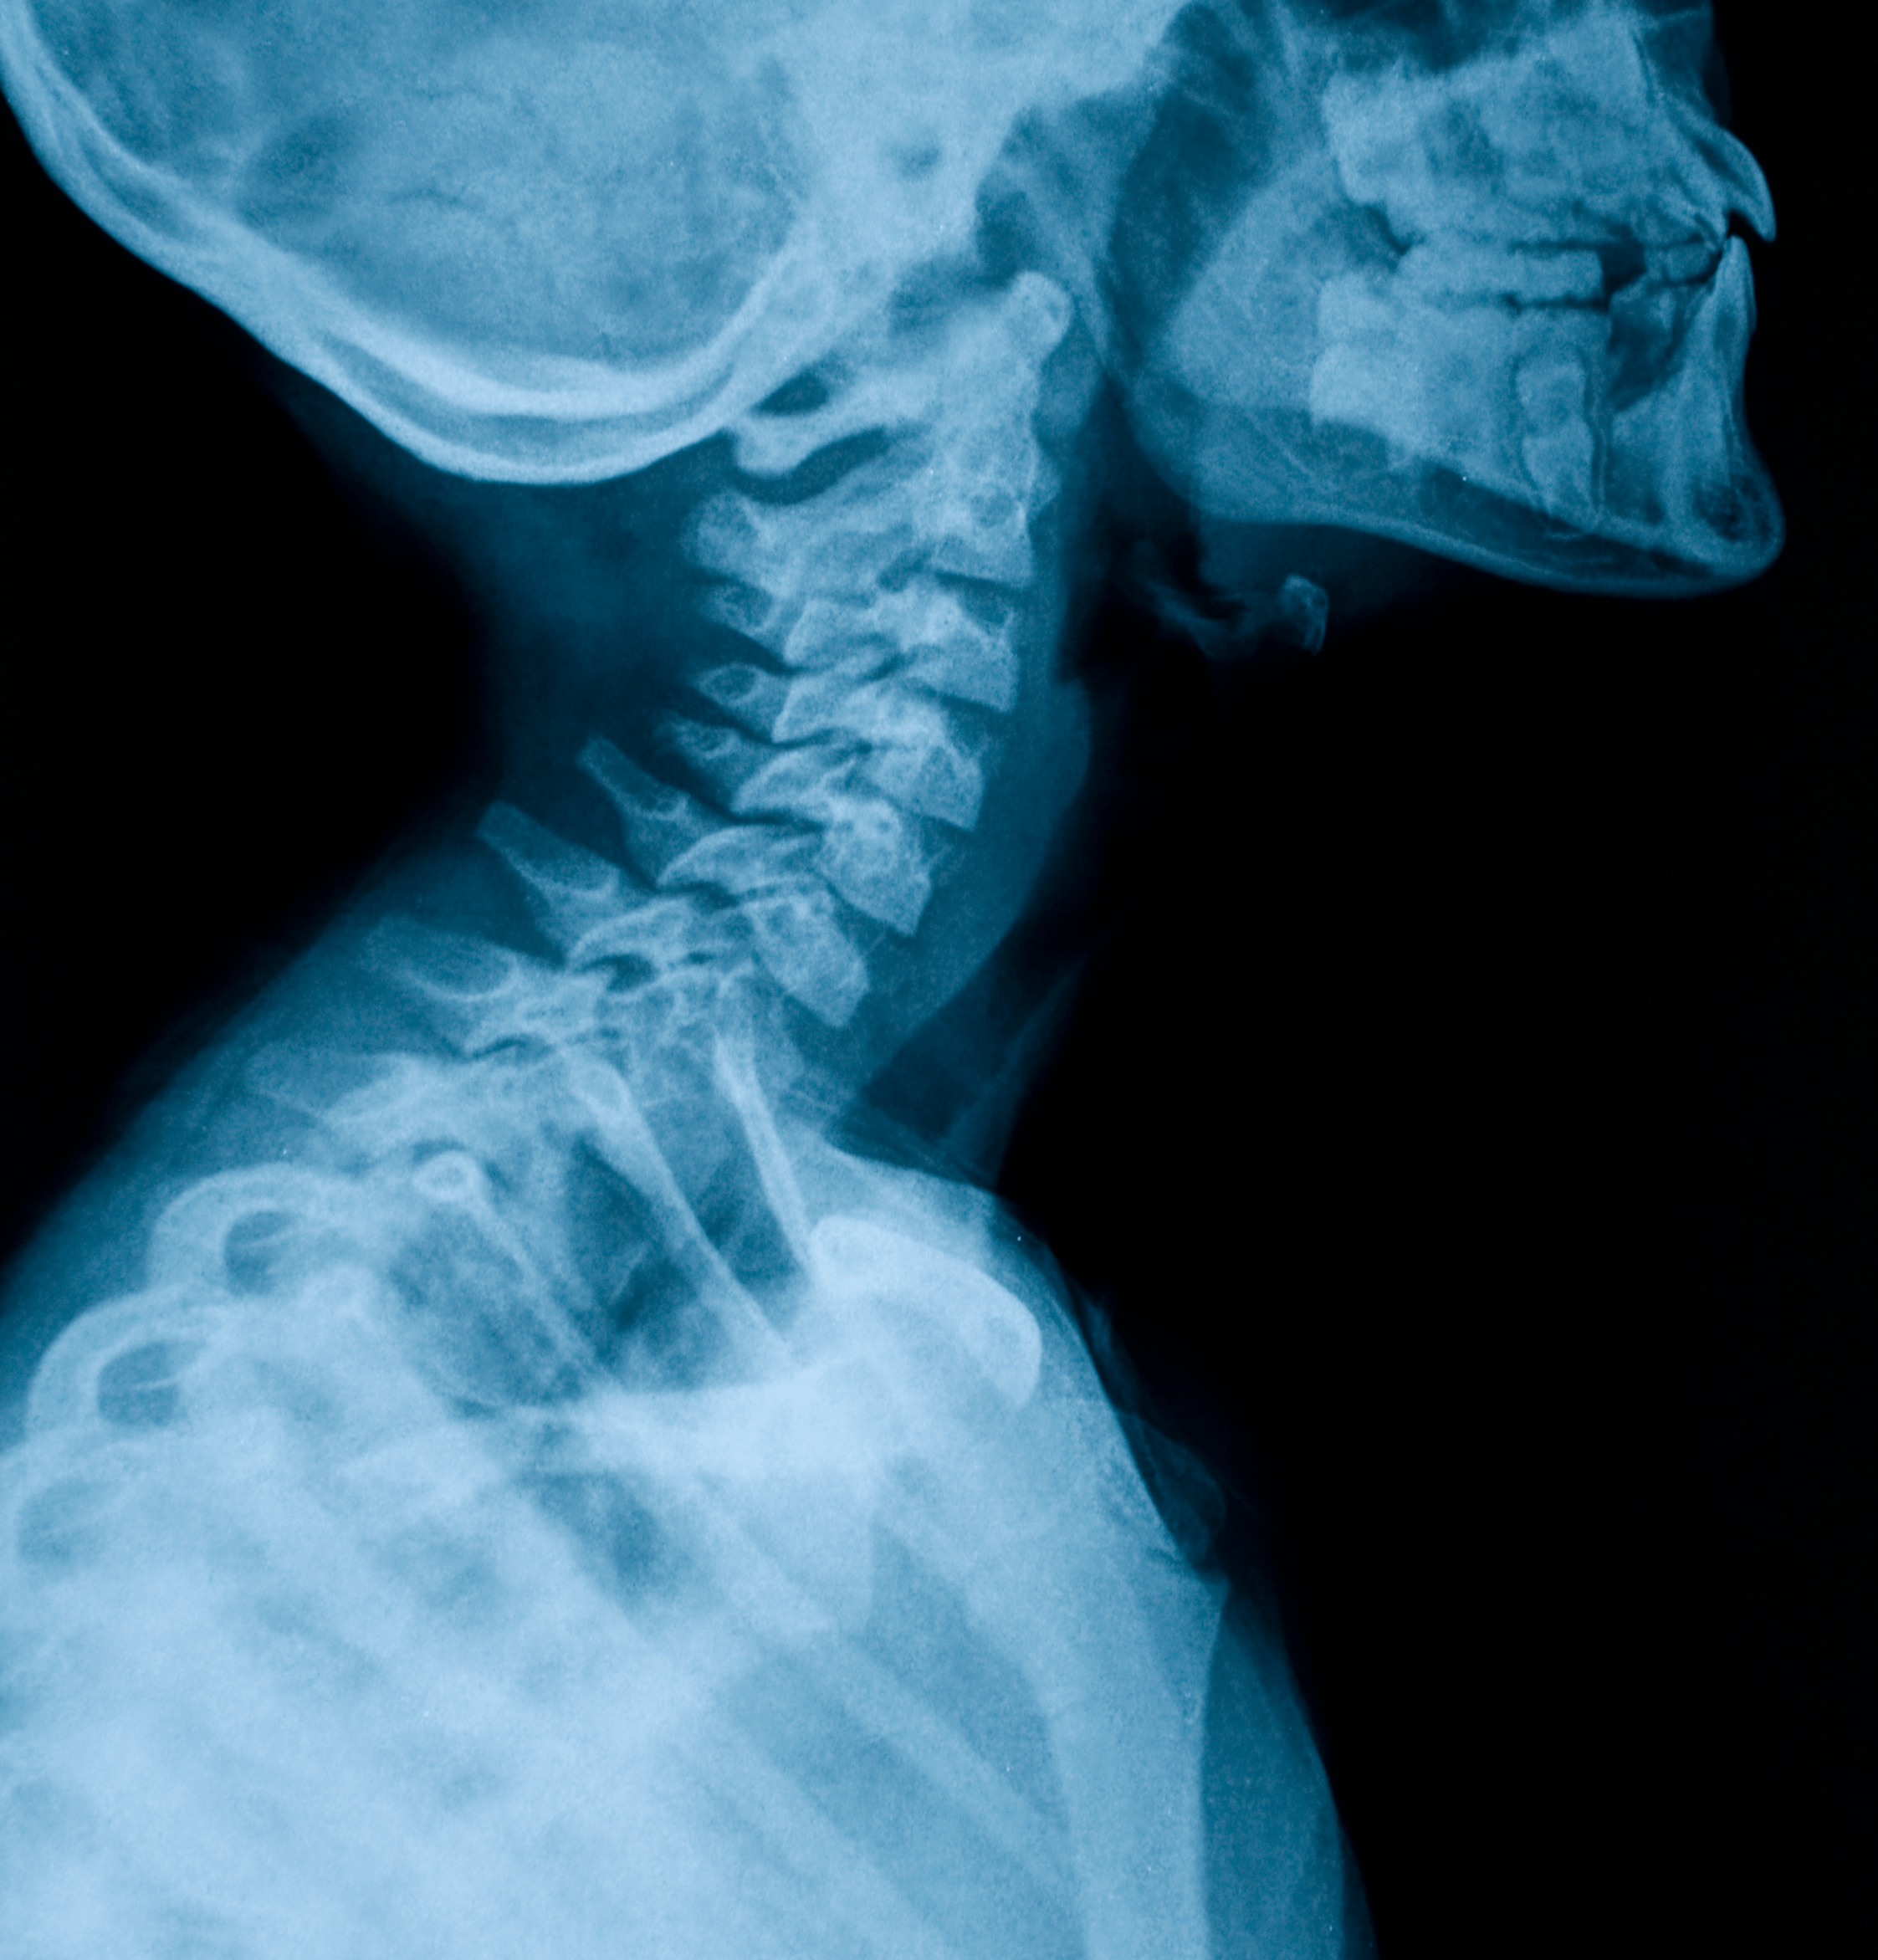

Radiografia cervicale a domicilio

Radiografia cervicale

Che cos'è la radiografia cervicale?

La radiografia cervicale è un esame diagnostico che utilizza i raggi X per ottenere immagini dettagliate delle strutture della regione del collo, in particolare della colonna cervicale

Questo esame permette di visualizzare le ossa della cervicale, inclusi i sette vertebre cervicali, e le strutture adiacenti come i dischi intervertebrali e le articolazioni

La radiografia cervicale viene eseguita utilizzando un fascio di raggi X che attraversa il collo e si imprime su una pellicola o un rilevatore digitale, creando immagini radiografiche.